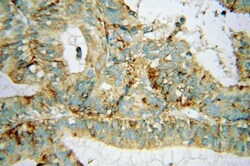

Supportive validation

- Submitted by

- Invitrogen Antibodies (provider)

- Main image

- Experimental details

- Immunohistochemistry of paraffin-embedded human ovary tumor using 15319-1-AP (AP3S2 antibody) at dilution of 1:100 (under 10x lens).